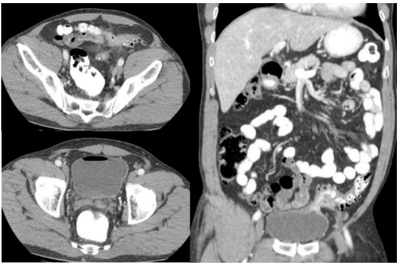

Homem, 55 anos de idade, encaminhado ao ambulatório de Urologia por infecções urinárias de repetição. O quadro teve início há três meses, com dor abdominal em hipogástrio e fossa ilíaca esquerda, quando procurou o pronto-socorro e foi identificada leucocitúria, recebendo tratamento com antibioticoterapia via oral. Um mês após, apresentou episódios frequentes de disúria e polaciúria, procurando o pronto-socorro por diversas vezes desde então. Há uma semana, iniciou com episódios de pneumatúria. Ao exame físico, encontra-se em bom estado geral, com abdome globoso, flácido e indolor, com desconforto à palpação de hipogástrio. Realizou a tomografia de abdome visualizada a seguir:

O quadro clínico do paciente é decorrente de: